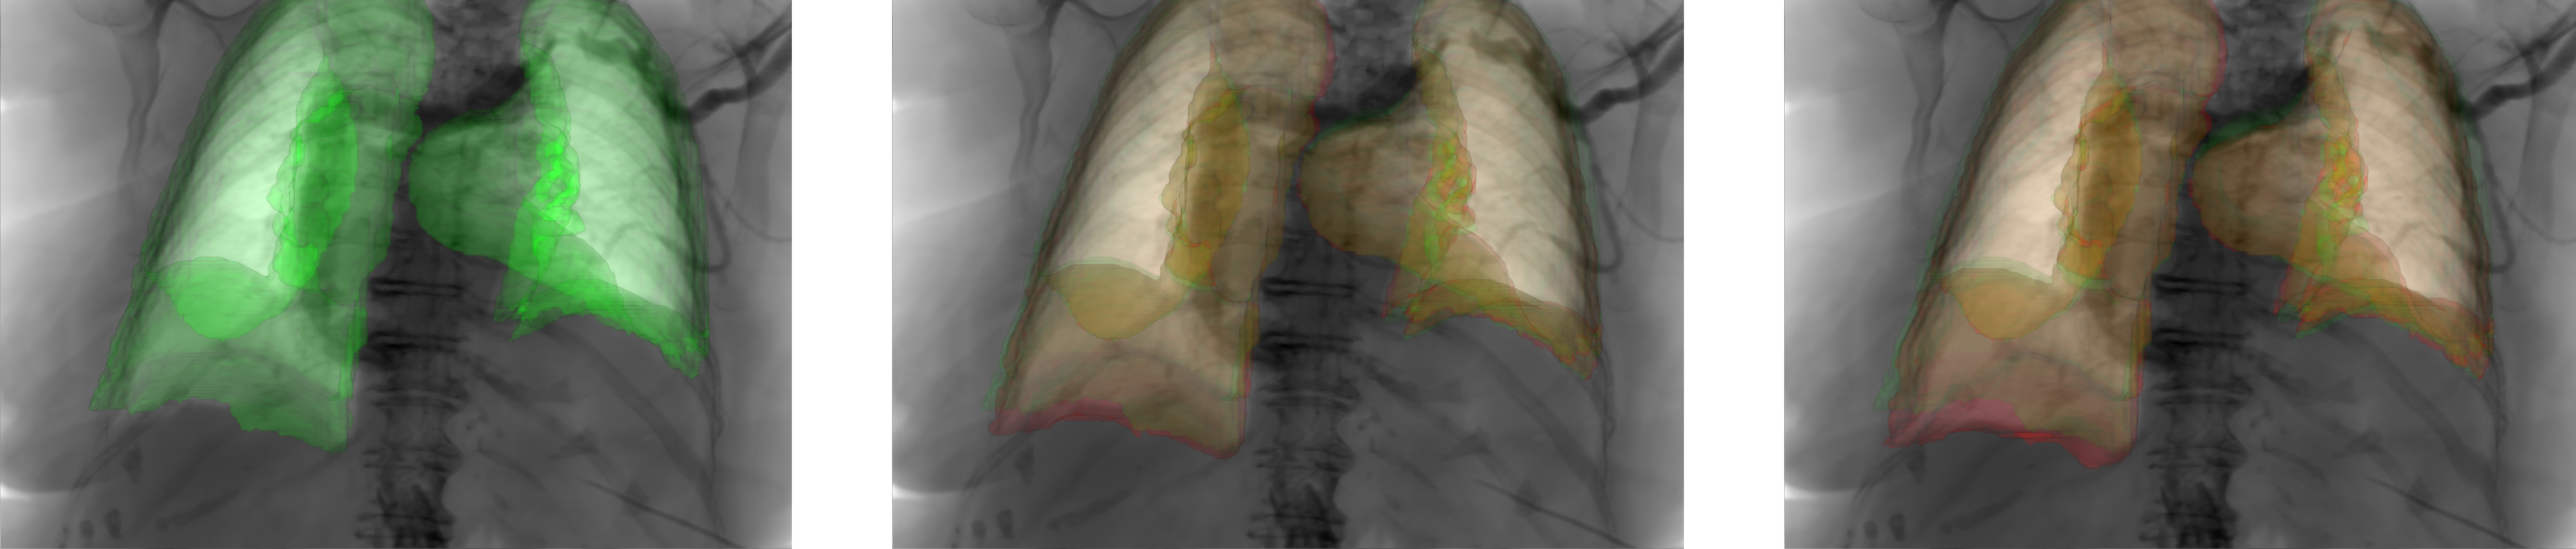

This level of accuracy is obtained at an update rate of about 20 Hz,

sufficient for interactive visualization of an augmented fluoroscopic image as illustrated in figure 3, or for real-time 3D navigation.